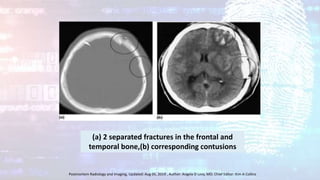

(a) 2 separated fractures in the frontal and

temporal bone,(b) corresponding contusions

Postmortem Radiology and Imaging, Updated: Aug 05, 2019 , Author: Angela D Levy, MD; Chief Editor: Kim A Collins

(a) 2 separatedfractures in the frontal and temporal bone,(b) corresponding contusions Postmortem Radiology and Imaging, Updated: Aug 05, 2019 , Author: Angela D Levy, MD; Chief Editor: Kim A Collins